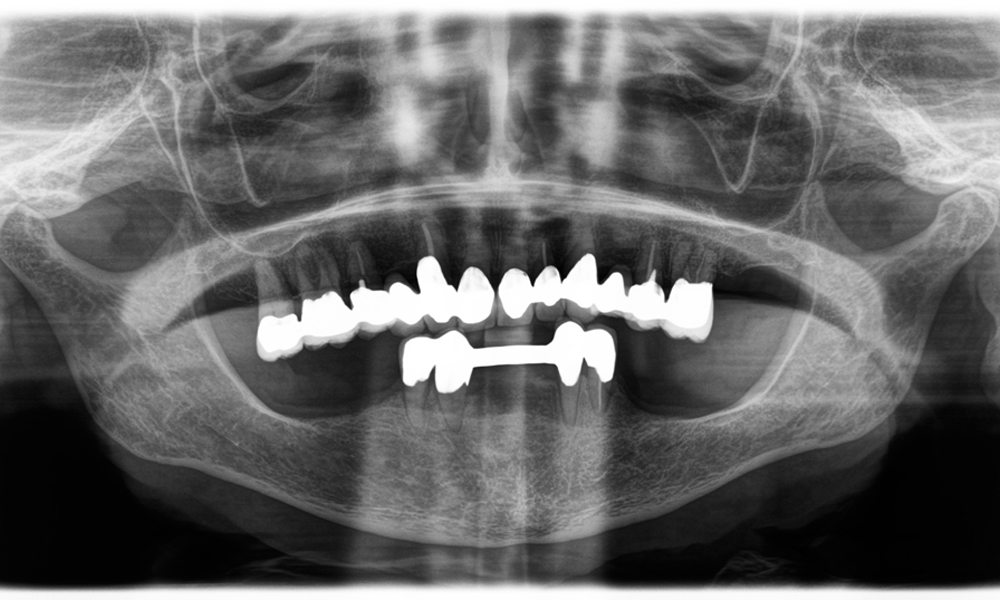

Otro ejemplo del rendimiento clínico de Power Edition fue la sustitución de una corona de zirconio dañada en una paciente de 63 años. El daño se produjo debido a la rotura de una parte del revestimiento de la corona de zirconio de 20 años de antigüedad en el diente 6. A pesar de encontrarse en la zona posterior, a la paciente le molestaba y deseaba una nueva corona.

La

Power

Edition

permitió

un

corte

preciso,

en

el

que

aumento

del

torque

y

mejora

de

refrigeración

contribuyeron

a

extraer

corona

sin

una

pérdida

significativa

material.

sistema

sujeción

mejorado

resultaron

ser

esenciales

este

sentido.